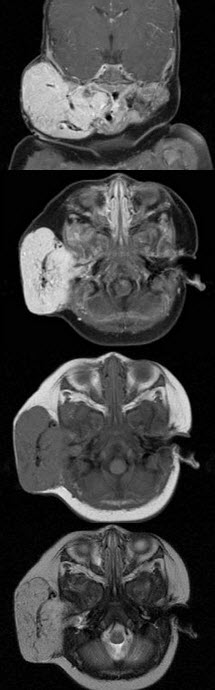

老年患者,右侧面部肿胀,呈青紫色,MRI检查如图所示,请选择最可能的诊断()A: 血管瘤B: 囊肿C: 脓肿D: 神经纤维瘤E: 神经鞘瘤

老年患者,右侧面部肿胀,呈青紫色,MRI检查如图所示,请选择最可能的诊断()

- A: 血管瘤

- B: 囊肿

- C: 脓肿

- D: 神经纤维瘤

- E: 神经鞘瘤